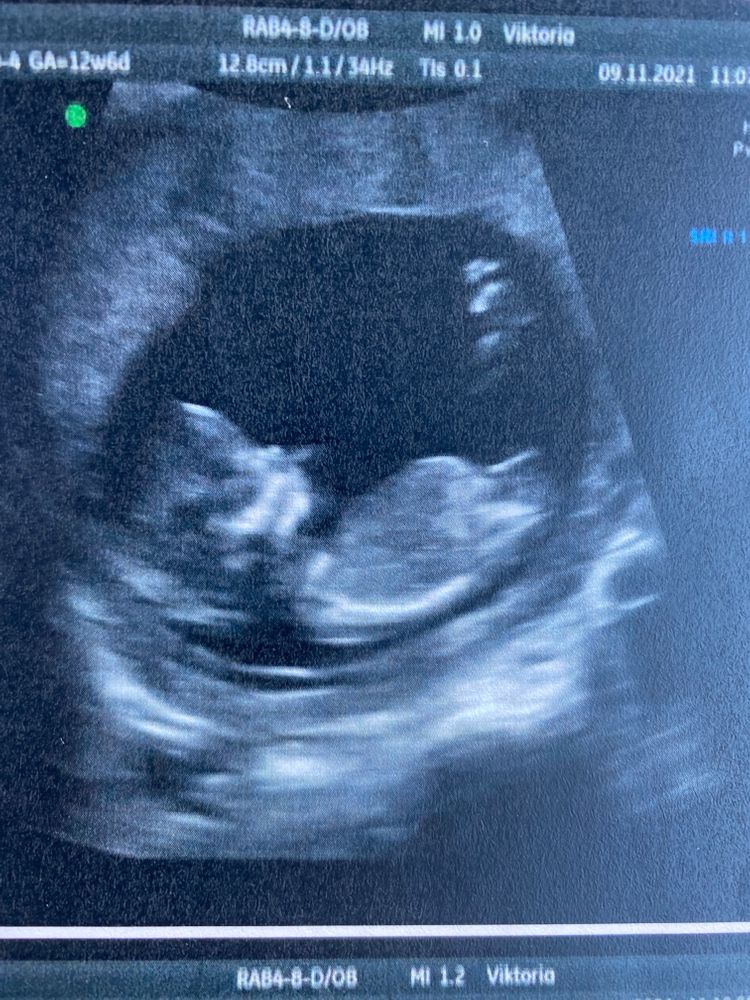

Первый скрининг! Фух!

Сашенька, какая радость! Поздравляю вас сильно сильно! Мне вот на первом скрининге сказали, что вообще видно, 50х50! В пятницу иду на плановое узи 15,5 недель, тоже очень надеюсь на девчушку! Но главное здоровый чтоб был) такая красоточка, прям личико уже видно махонькое 🤗🤗🤗

Мне сказали так: девочка ещё может стать мальчиком, а вот мальчик точно. Но врач тоже ещё в 12 недель увидела девочку, в 16 подтвердила:)

Мне на 12 недели предположили девочку, расположение малышки похоже с вашим) ну и половая часть тоже. Муж пойдет на 2 скрининг) На самом деле в платных клиниках говорят пол на 1 скрининге.